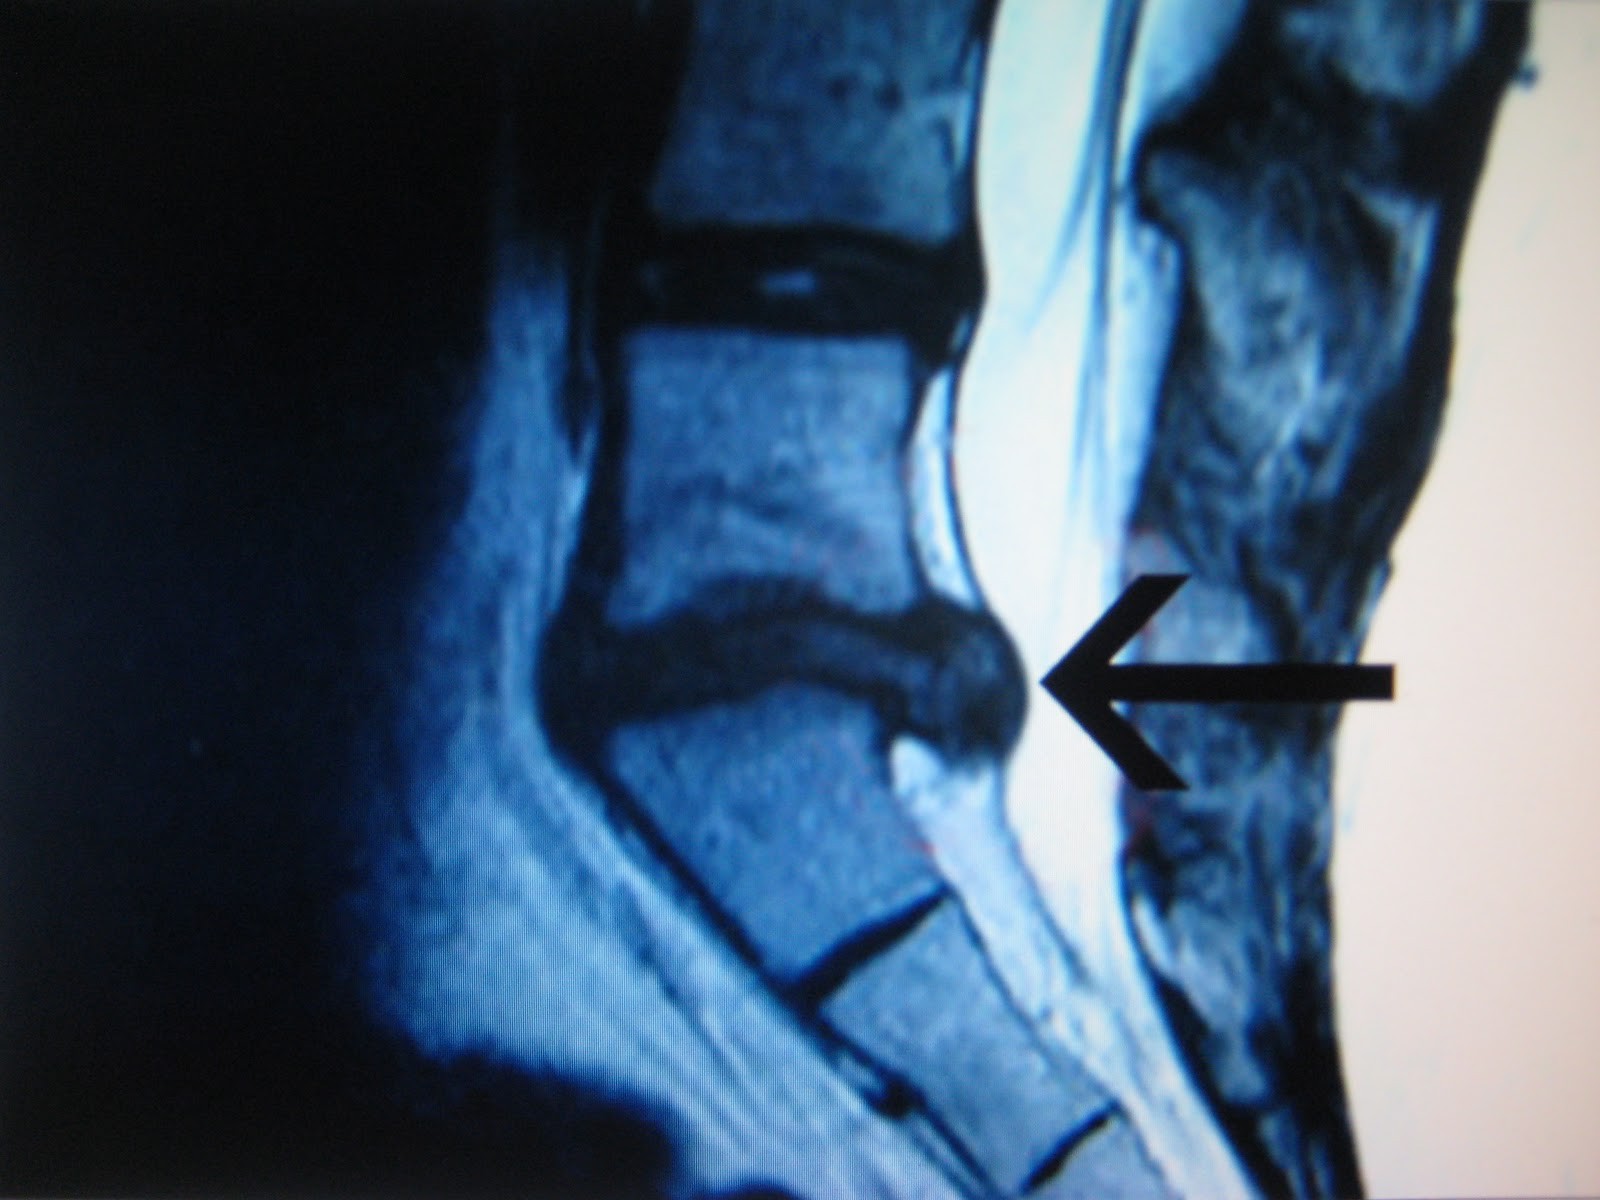

در بسیاری موارد پزشک می تواند دیسک آسیب دیده را تشخیص دهد. برای تائید این موضوع، پزشک برای شما CTscan یا MRI تجویز خواهد کرد.

در مواردی که CTscan و یا MRI نتوانند عامل درد را تشخیص دهند ممکن است از روش تصویر برداری میلوگرافی استفاده شود. در این روش یک ماده حاجب به داخل کانال نخاع تزریق می شود، و سپس از ستون فقرات فرد تصویر برداری به عمل می آید.

تشخیص نوع تصویر برداری بر عهده ی پزشک است. این کار باید با دقت انجام شود و بعد از مشاهده هر گونه علائم خطرناکی باید بلافاصله اقدامات درمانی انجام شود.